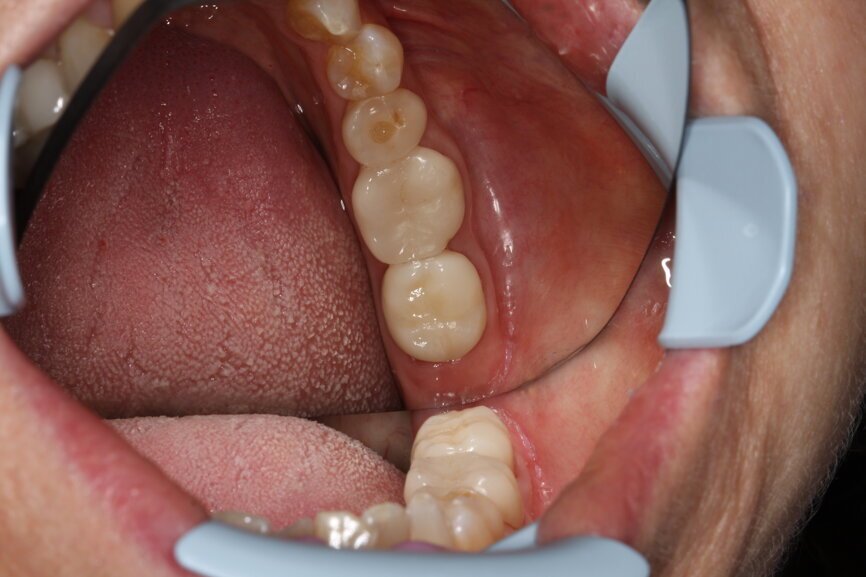

A case history demonstrates how CEREC Primescan proves its worth in everyday practice. A patient came to the practice with an inadequate crown, with secondary caries, in position #37. After excavation, a new CEREC crown was to be mounted. In order to do so, the new acquisition centre, CEREC Primescan AC, with its significantly larger, tiltable touch screen, was first disinfected. Thanks to the seamless surfaces, it is possible to do so quickly, thoroughly and simply, at any time. Before beginning with the scans, the patient data was retrieved in CEREC Primescan AC, and a new case was created. Overall, the scanner was used three times during treatment: after preparation of the lower dental arch with tooth #37, for the scan of the opposing dental arch and for the scan of the buccal bite on both sides.

After removal of the inadequate crown and the final preparation, it was time to use the CEREC Primescan. Dr Stamnitz describes it as follows: “As a long-time user of a CEREC Omnicam, I realised immediately that CEREC Primescan felt different in my hand. The scanner is even better balanced. The actual scanning is quick and easy—partially due to the fact that I don’t have to consider specific scanning angles or scan procedures. It all went intuitively and fluidly. The full dental arch scan was completed in less than a minute, which certainly cannot be taken for granted. What made it really special was that the patient was immediately able to see the results on the monitor with me. The scan was converted into a 3D image immediately. Compared with previous scanners, I noticed immediately that it is also able to scan other materials, such as gold crowns. Therefore, no information on the adjacent teeth or antagonists was lost. I consider that to be real progress.”